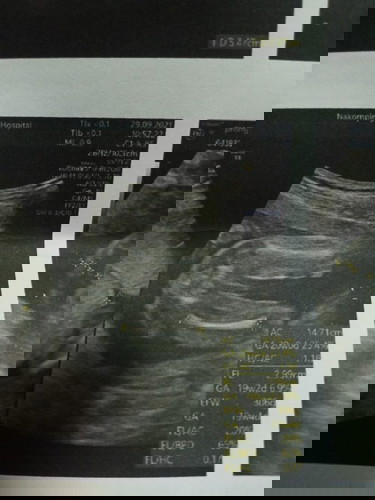

คุณหมอบอกว่าน้องเป็นเพศชาย แต่แม่ดูภาพอัลตร้าซาวด์ไม่ออก แบบนี้เป็นจู๋หรือจิ๋มน้องคะ😅รบกวนแม่ๆช่วยดูให้หน่อยนะคะ #ขอบคณุสำหรับคำตอบนะคะท้องแรกค่ะ❤

ชายจ้า เหมือนเราเลย พึ่งไปซาวมาเสาร์ที่ผ่านมาจ้า 17 วีค ทั้งไข่ ทั้งจู๋มาเต็ม

ปิกก้าจู๋ น้องชัดมากเลยค่ะ😊😁

ชายจ้าแม่ จู๋ยาวออกมากเลย😁

ปืนอยู่ตรงกลางจ๊ะแม่

ชายจ้ะเห็นชัดมากค่ะ